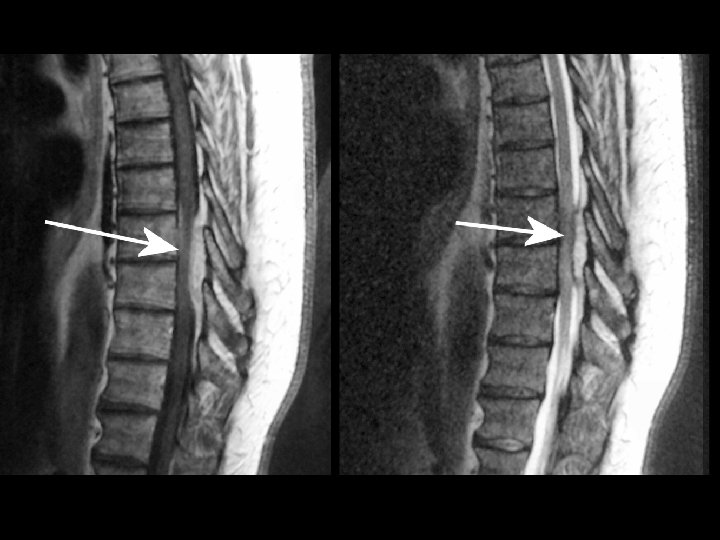

Radiculopathy: Etiology • Structural – Disk – Spondylosis – Tumor – Abscess – Hematoma